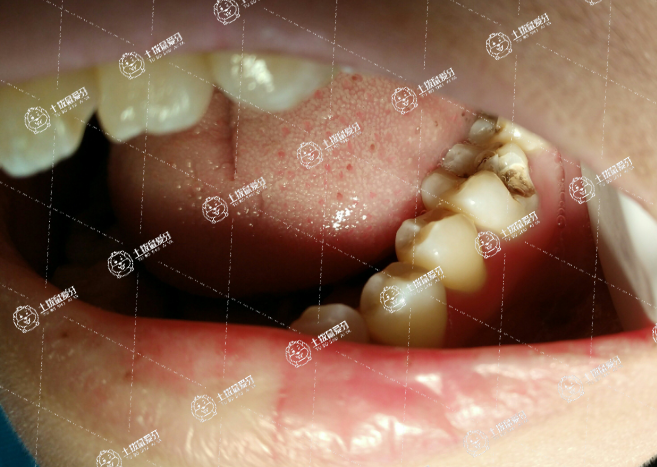

口腔健康是兒童健康的重要方面,作為家長,也是非常擔(dān)心自家孩子出現(xiàn)齲齒的可能性,畢竟孩子在出現(xiàn)齲齒后往往還是會(huì)給整個(gè)身心健康會(huì)造成極大的影響與傷害,及時(shí)做補(bǔ)牙修復(fù)是當(dāng)下非常重要的事情,怎么補(bǔ)牙齒洞比較好?這或許是牙友們比較在意的事情,接下來,我們一起來了解一下.

選擇合適的才是最好的。牙齒有個(gè)小洞,平時(shí)沒有疼痛的問題,去腐質(zhì),制備好一定的洞形,用樹脂材料補(bǔ)上就很好。若是出現(xiàn)一定的冷熱刺激疼痛,最好在樹脂材料下面墊一層墊底材料,可以減少對牙神經(jīng)的刺激,也可以促進(jìn)牙本質(zhì)的修復(fù)。

若是出現(xiàn)自發(fā)性疼痛或者咬合時(shí)疼痛,就應(yīng)該失活牙神經(jīng),做根管治療了。根管治療完畢,應(yīng)該戴一個(gè)金屬或者烤瓷冠進(jìn)行保護(hù)牙齒,以免咬硬的食物時(shí)牙冠破裂。

補(bǔ)牙適用于牙齒有缺損以及有齲壞的人群,補(bǔ)牙的方式有很多,選擇適合自己的方式非常重要。